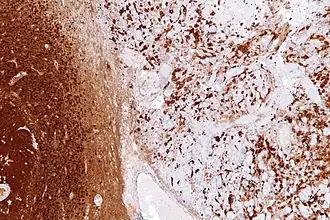

Reactive astrogliosis is the most common form of gliosis and involves the proliferation of astrocytes, a type of glial cell responsible for maintaining extracellular ion and neurotransmitter concentrations, modulating synapse function, and forming the blood–brain barrier.[3] Like other forms of gliosis, astrogliosis accompanies traumatic brain injury as well as many neuropathologies, ranging from amyotrophic lateral sclerosis to fatal familial insomnia. Although the mechanisms which lead to astrogliosis are not fully understood, neuronal injury is well understood to cause astrocyte proliferation, and astrogliosis has long been used as an index for neuronal damage.[4] Traditionally, astrogliosis has been defined as an increase in intermediate filaments and cellular hypertrophy as well as an increase in the proliferation of astrocytes. Although this hypertrophy and proliferation in their extreme form are most closely associated with the formation of a glial scar, astrogliosis is not an all-or-none process in which a glial scar forms. In fact, it is a spectrum of changes that occur based on the type and severity of central nervous system (CNS) injury or disease triggering the event.[5] Changes in astrocyte function or morphology which occur during astrogliosis may range from minor hypertrophy to major hypertrophy, domain overlap, and ultimately, glial scar formation.[5] The severity of astrogliosis is classically determined by the level of expression of glial fibrillary acidic protein (GFAP) and vimentin, both of which are upregulated with the proliferation of active astrocytes.[4][6]